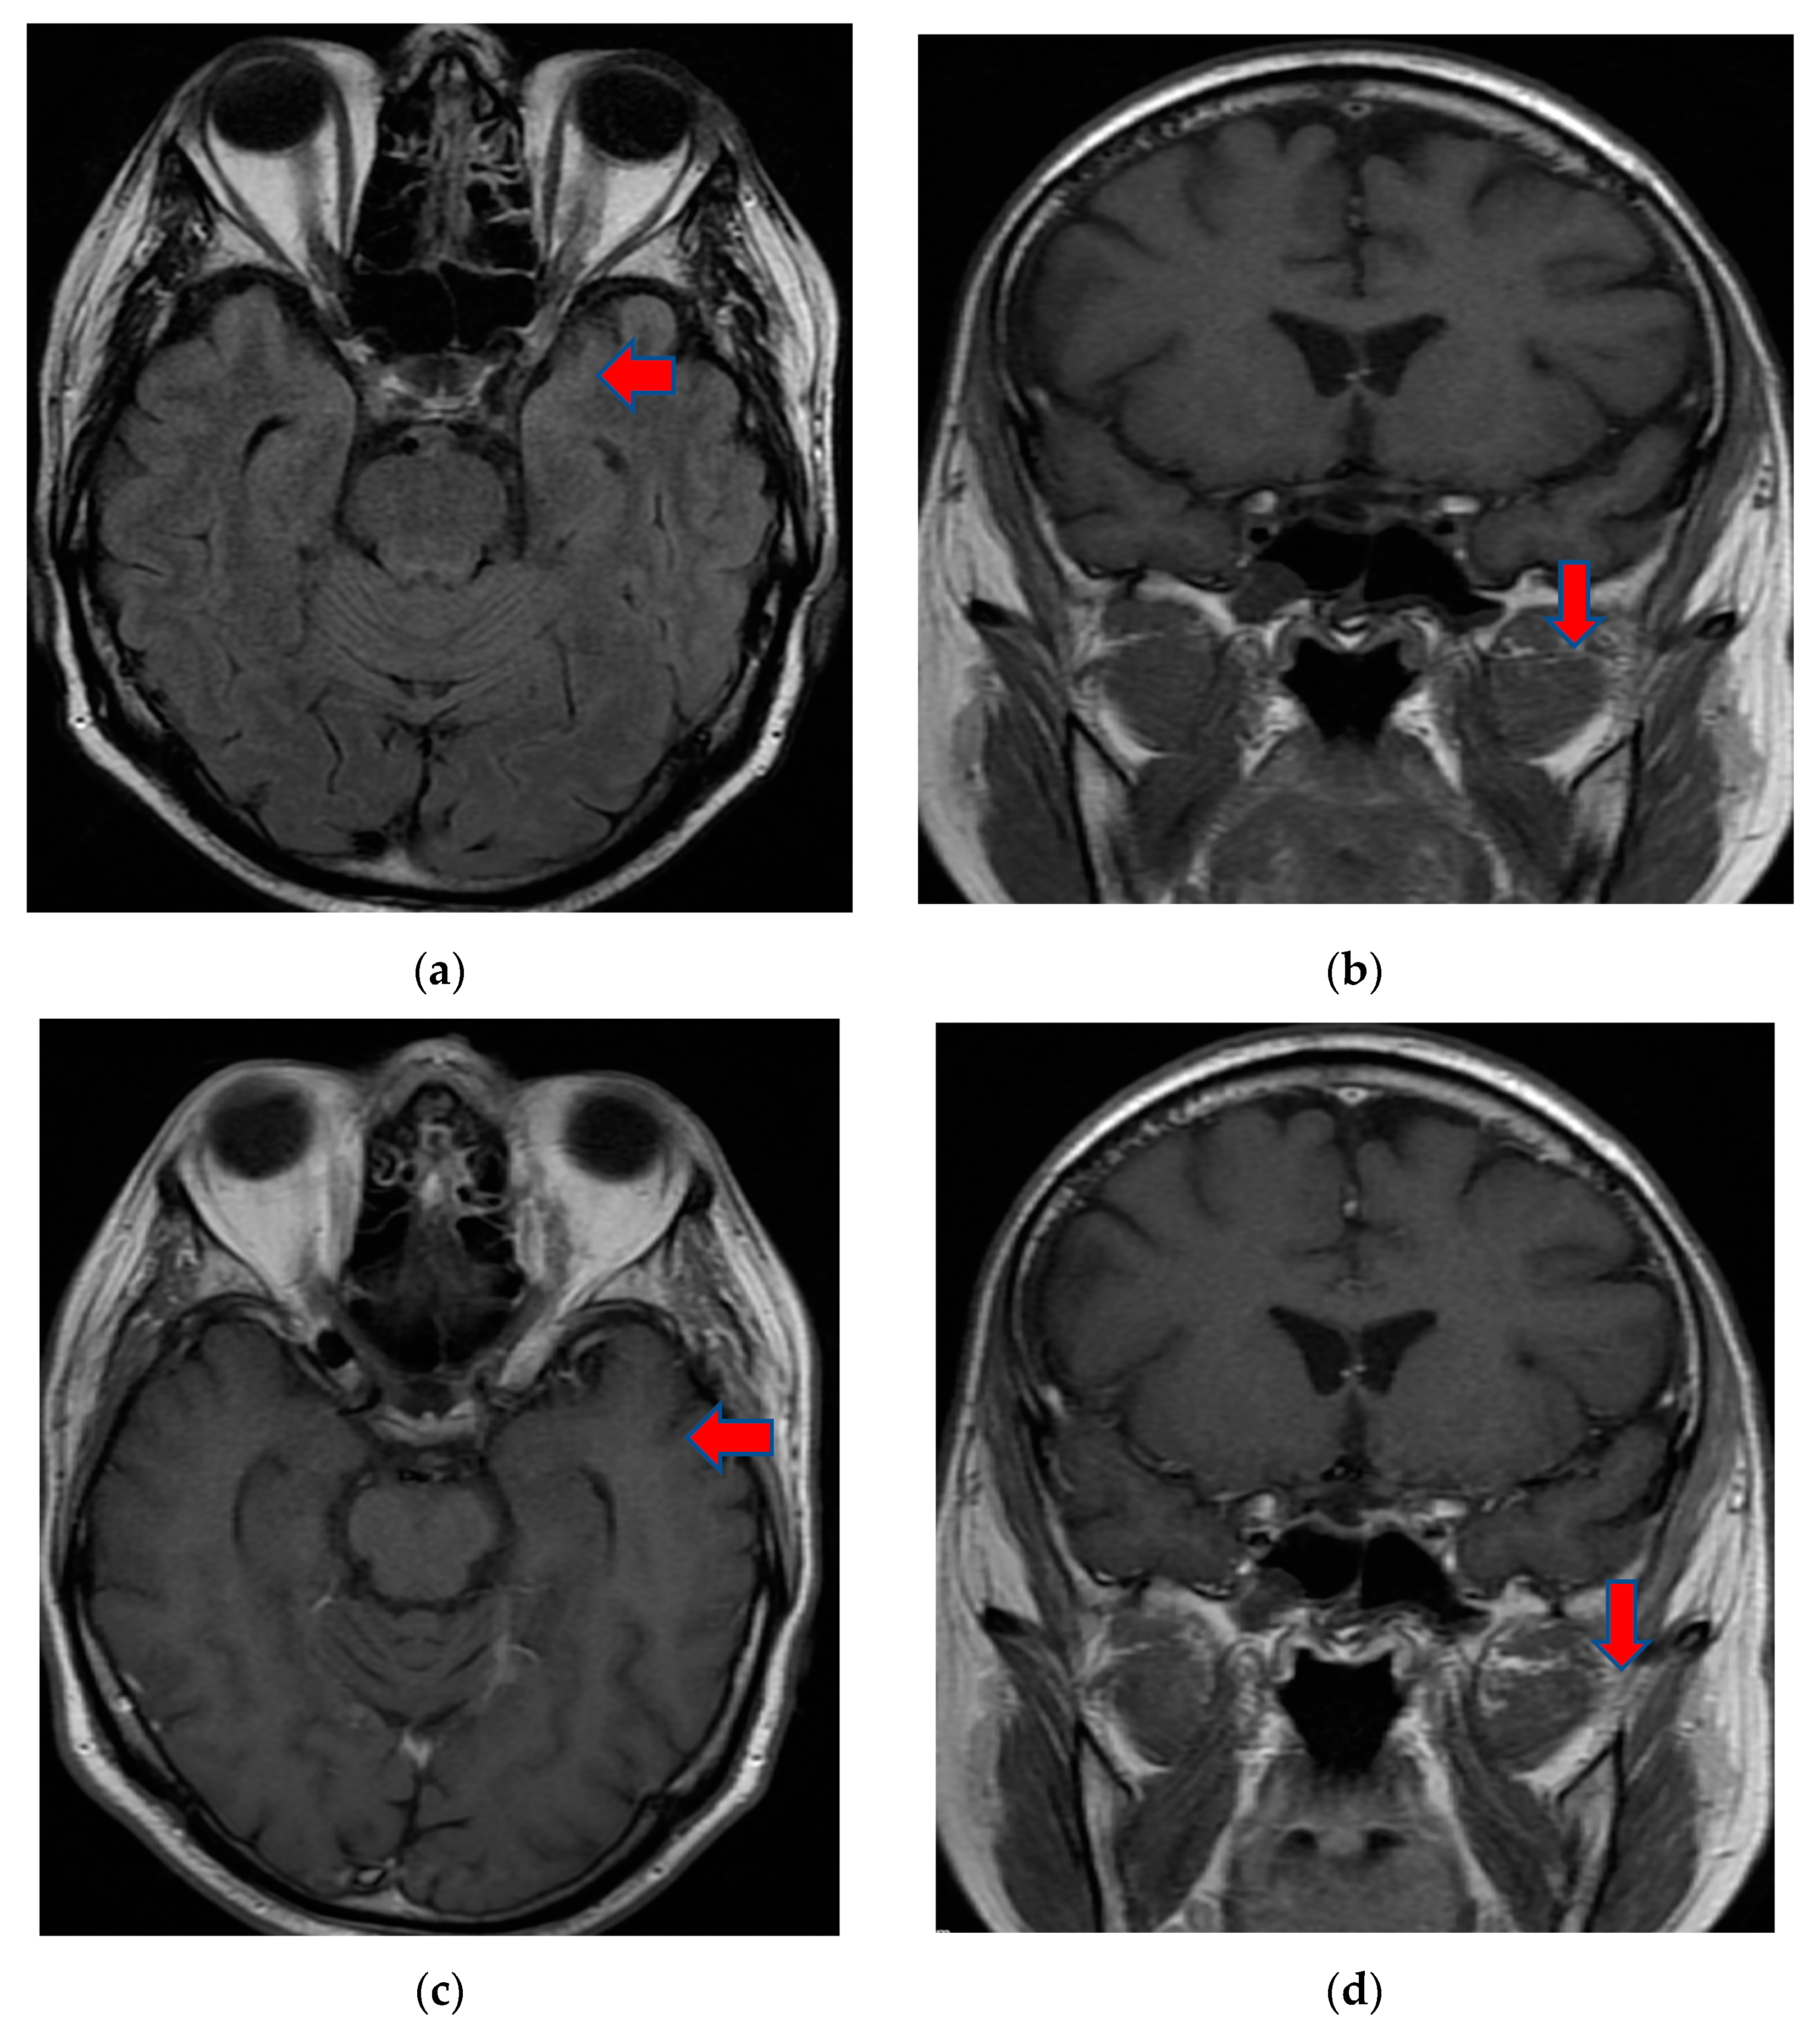

On day eight, the patient became comatose with altered neurological status and was intubated, with mechanical ventilation in the intensive care unit. He required i.v. fluids, pressors, ceftriaxone, vancomycin, and antifungals due to concerns regarding sepsis. A CT of the brain was obtained in light of the acute hemorrhage of intraparenchymal fronto-parieto-temporal lobes, showing important edema (Figure 4).

Figure 4. (a,b), Brain-CT showed acute hemorrhage of intraparenchymal fronto-parieto-temporal lobes with important edema and ventricular extension.